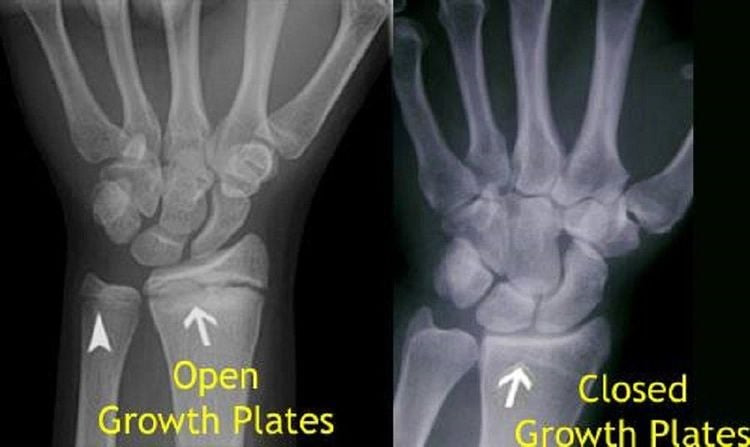

Now, to find out if your growth plates are fused or not, we’re going to look at your wrist & knees for your height, and at your clavicles for your frame.

Above I've added 3 figures, from open ( A ) to fully fused ( C ), those are your growth plates, if theres a visible line like in B, they’re still open, but closer to fusion. ( You will typically see this in X-rays of teenagers). Whereas if you don’t see any lines at all, it means the cartilage has hardened into solid bone, ending any growth potential.

Once again, refer to the graphic above.

If there’s a visible gap or a full line, your growth plates are open, if there’s no visible line, they’re closed.